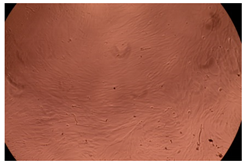

2.4. In Vitro Cytotoxicity Analysis

| Sample | 24 h | 48 h | |

|---|---|---|---|

| Control |  |  | |

| Cop B | 10 µg/mL |  |  |

| 50 µg/mL |  |  | |

| 100 µg/mL |  |  | |

| Cop B/IMC = 10/1 (wt/wt) | 10 µg/mL |  |  |

| 50 µg/mL |  |  | |

| 100 µg/mL |  |  | |

| Cop B/Dorzolamide = 10/1 (wt/wt) | 10 µg/mL |  |  |

| 50 µg/mL |  |  | |

| 100 µg/mL |  |  | |